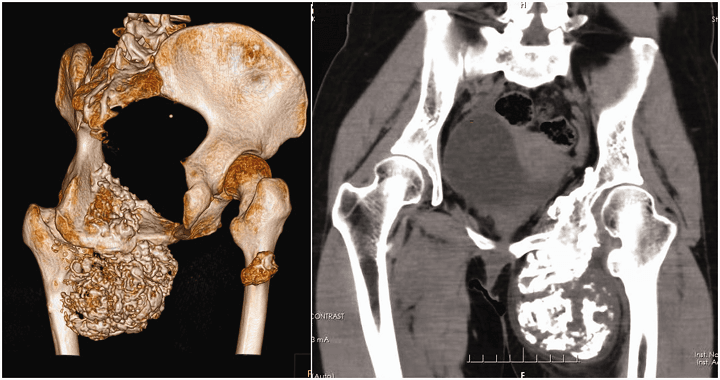

3D printing has been used before to make customized pelvic implants for patients. In this case, a 29-year-old woman presented with a lump that had been growing in her left thigh for ten years, and while she had no pain – common with chondrosarcoma – the patient was having some mobility issues. After an X-ray showed a giant tumor “eroding the pubic bone, ischium, and acetabulum,” she was admitted, and further testing showed that the tumor, diagnosed a mucinous chondrosarcoma with a fine needle biopsy, had invaded her inner thigh and shifted her left femoral artery and deep femoral artery.

“Although titanium alloys are widely used in orthopedic surgeries because of their outstanding biocompatibility and biomechanical characteristics, some reports have described implant loosening and bone resorption due to the stress shielding effect after the application of titanium implants,” they wrote. “To avoid this effect, we used a porous structure 3D painted implant in which the diameter of each aperture was 200 µm, the extent of porosity was 38%, and the density was 2.8 g/m3. Suture anchors for fixation of the muscles and ligaments were designed on the implant according to the 3D-reconstructed CT data.”

During the five-hour surgery, doctors used the 3D printed guide to isolate and resect the tumor once the iliac periosteum was exposed. When they said massive, they meant it – the tumor measured at 12 × 8 × 6 cm. Luckily, they were able to get clear margins.

After the left superior acetabulum, pubic symphysis, and femoral neck were resected, they removed the cartilage on the right pubic symphysis and used screws to affix the 3D printed titanium implant onto the “bleeding bone bed.” The hip was externally rotated in order to expose the femoral neck, “which was then sawed 1 cm superior to the lesser trochanter” before the hip joint was re-positioned. The position of the implants was confirmed using intraoperative C-arm X-ray, and then the hip joint was dislocated. The surgeons filled a 3D printed acetabulum with bone cement, before a polyethylene socket was fixed inside. Once the cement solidified, they inserted femoral stem and femoral head prostheses and restored the joint.